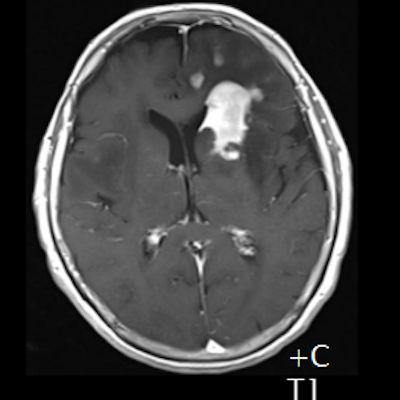

- (B) Aksiyel postkontrast T1A görüntülerde büyüğü sol frontalde kontrastlanma gösteren multipl kitle lezyonları (oklar) izlenmektedir.

- Olguda tanı sol frontalde kontrast tutan lezyondan yapılan beyin biyopsisi ile konulmuştur.

- Kitleler çoğunlukla solid ve homojendir.